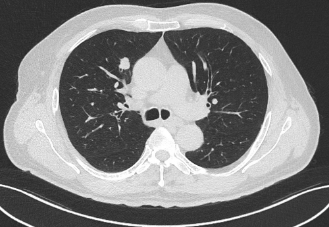

近日,昭通市中医医院呼吸与危重症医学科二科成功为一名合并多种基础疾病的61岁肺癌患者实施了昭通首例经口支气管镜超声(EBUS)引导下肺癌冷冻消融术。该患者因“反复咳嗽、咳痰1年,确诊右肺鳞癌2月余”入院。胸部增强CT显示其右肺上叶存在两个高危结节(Lung-RADs 4X类),同时合并慢性支气管炎伴肺气肿、肺炎、冠心病(支架术后)、肺大疱、肺不张等疾患。

术前患者CT